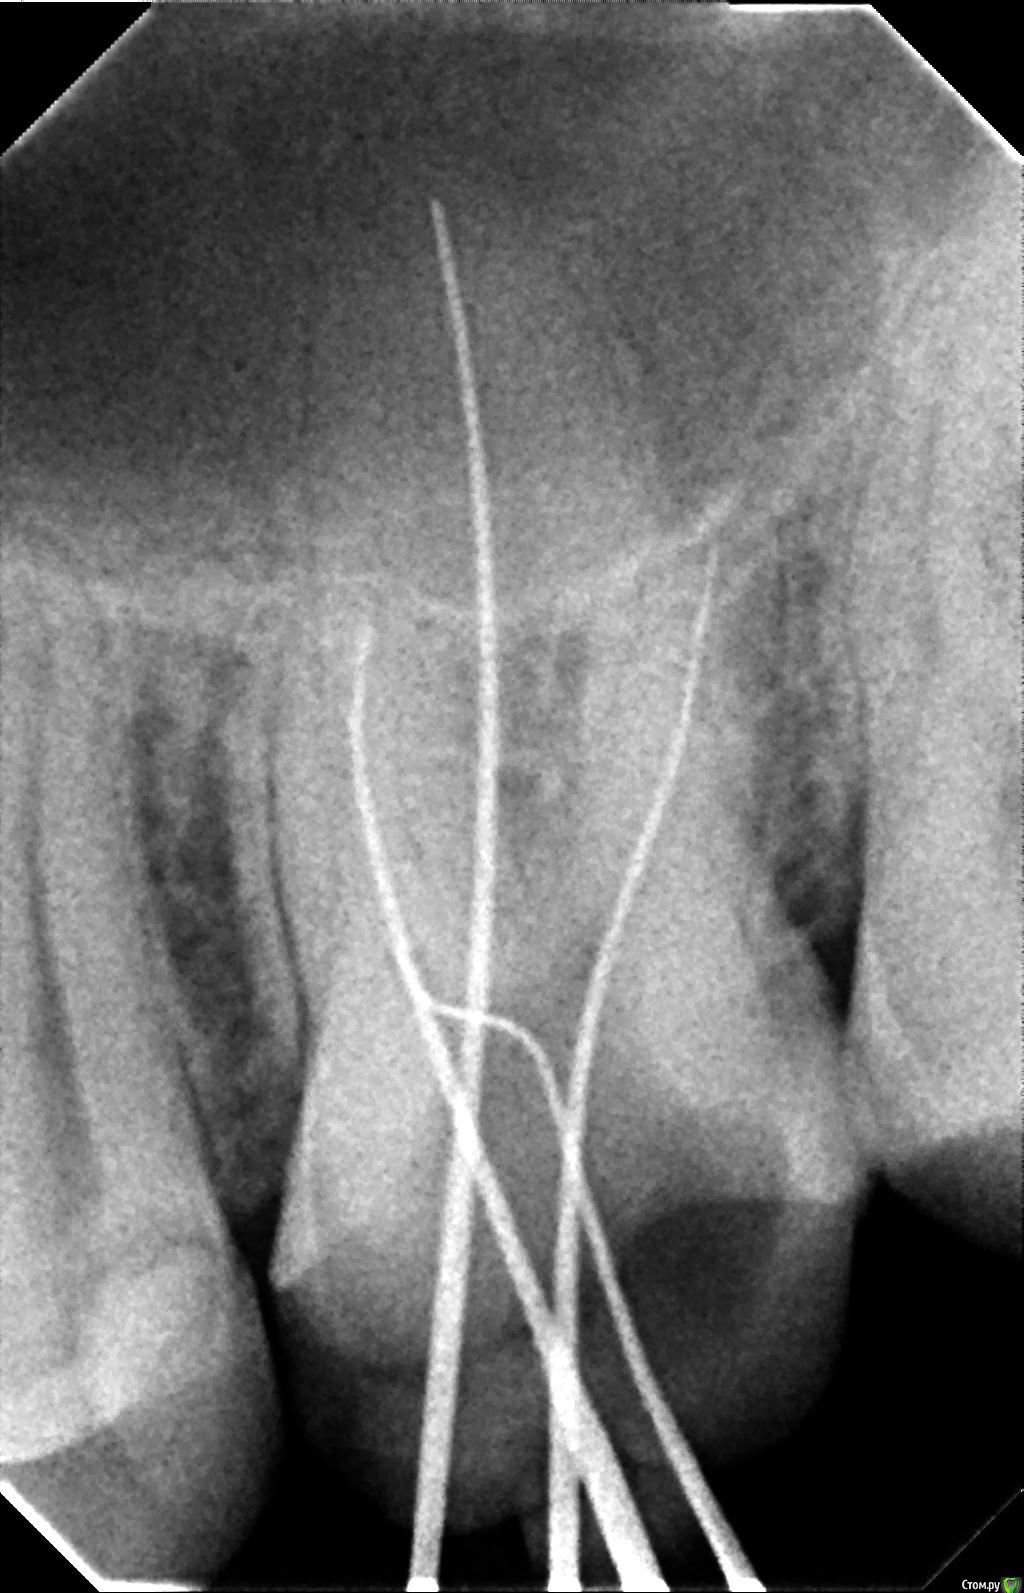

К сообщению прикреплены фотографии процесса лечения 26-го зуба.

После пломбировки каналов, я решил пойти ставить коронку в другую клинику, но там мне сказали, что не дают гарантию на этот зуб, поскольку каналы не долечены, и что я могу обратиться по гарантии в первую клинику. Но в первой клинике мне сказали, что все долечено. Хочу узнать мнение специалистов по этому поводу. Должен ли канал очищаться и пломбироваться до самой границы корня? Видно ли, что зуб не долечен по этим снимкам?

Так же в первой клинике в процессе лечения мне говорили, что у меня в зубе 5 каналов. Из-за этого цена лечения должна была быть еще дороже, но сказали, что мне оказали благосклонность и вылечили пятый канал бесплатно. В другой клинике мне сказали, что информация про 5-й канал - это ложь.